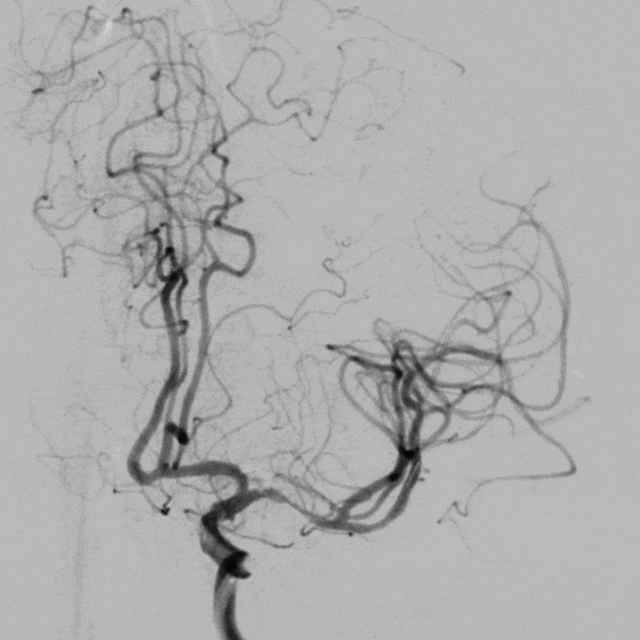

术前造影提示:左侧大脑中动脉闭塞,可见部分豆纹动脉显影,左侧大脑前动脉通过脑膜支代偿左侧大脑中上干。

中年男性患者,起病急,病情有进展加重表现,造影提示左侧大脑中动脉近端以远闭塞,大脑前部分代偿,造影闭塞为椎形征,考虑脑梗死发病机制为ICAS可能性大。拟行“BASIS技术”取栓及开通左侧大脑中动脉闭塞必要行支架植入术治疗。

0.014" 微导丝引导下支架微导管进入M2下干,保留导丝退回微导管,造影提示M2未见显影,考虑“首过效应”阴性。此时考虑病变性质狭窄基础上并大负荷血栓可能,不排除栓塞性病变可能。

沿微导管送入4.0*30mm Syphonet®取栓支架,造影显示:造影见左侧大脑中动脉M1段约1.8cm细长狭窄显影。大脑中动脉一干仍不显影,考虑狭窄明显并血栓形成。以静脉替罗非班推注12ml,同时静脉7ml/h维持。